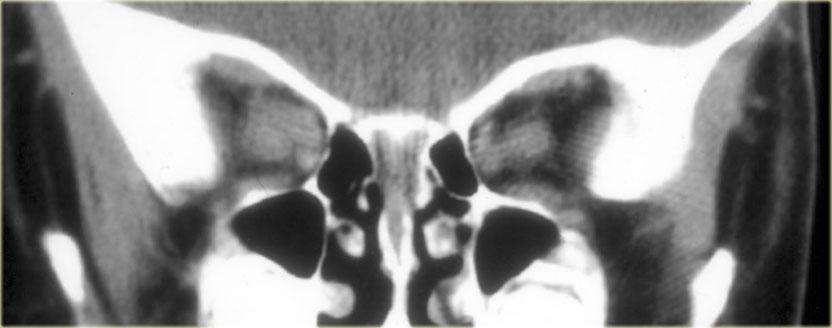

U Tuyến Yên Vi Thể

Theo định nghĩa, u tuyến yên vi thể có đường kính nhỏ hơn 10 mm và nằm trong tuyến yên.

Các hình ảnh này minh họa một trường hợp điển hình: trên chuỗi xung T1W, tổn thương có đường kính khoảng 3-4 mm, giảm tín hiệu nhẹ so với mô tuyến yên bình thường, nằm trong tuyến yên.

Trên chuỗi xung T2W, tổn thương tăng tín hiệu nhẹ.

Chẩn đoán phân biệt: u tuyến yên vi thể hoặc nang khe Rathke (hai thực thể này có thể không phân biệt được với nhau).

Độ nhạy của MRI không tiêm thuốc tương phản từ trong phát hiện u tuyến yên vi thể vào khoảng 70%.

Không phải lúc nào cũng cần tiêm thuốc tương phản từ đường tĩnh mạch để phát hiện u tuyến yên vi thể, vì những bệnh nhân có kết quả chụp âm tính thường nhận được phác đồ điều trị triệu chứng tương tự như bệnh nhân có u vi thể (thông thường đây là những phụ nữ có triệu chứng tăng prolactin máu).

Mục đích của việc chụp MRI là để loại trừ các tổn thương kích thước lớn.

Đối với các ứng viên có thể phẫu thuật (ví dụ: bệnh nhân thất bại với điều trị nội khoa hoặc bệnh lý tuyến yên không đáp ứng với điều trị nội khoa như bệnh Cushing), cần thiết phải tiêm thuốc tương phản từ để xác định vị trí tổn thương một cách chính xác nhất có thể.

Trên phim chụp không tiêm thuốc tương phản từ, có thể phát hiện khoảng 70% tổng số u tuyến yên vi thể.

Khi tiêm gadolinium, tỷ lệ âm tính giả có thể giảm từ 30% xuống còn 15%.

Như đã đề cập trước đó, điều này thường không ảnh hưởng đến quyết định xử trí lâm sàng của bệnh nhân.

Hình ảnh chuỗi xung T1W và T2W mặt phẳng coronal, cùng với hình ảnh chuỗi xung T1W trước và sau tiêm gadolinium.

Ở bệnh nhân này, tổn thương trong tuyến yên chỉ có thể phát hiện được sau khi tiêm thuốc tương phản từ đường tĩnh mạch.

Chẩn đoán phân biệt: u tuyến yên vi thể hoặc nang khe Rathke.